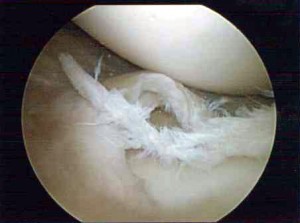

The torn flaps of cartilage can irritate or catch in the joint causing pain and swelling. Tears caused by injuries can be repaired or trimmed through keyhole surgery (knee arthroscopy). Only the tear is trimmed, leaving as much normal meniscus behind as possible. Degenerate tears are usually treated by trimming the tear as repair is not usually possible.